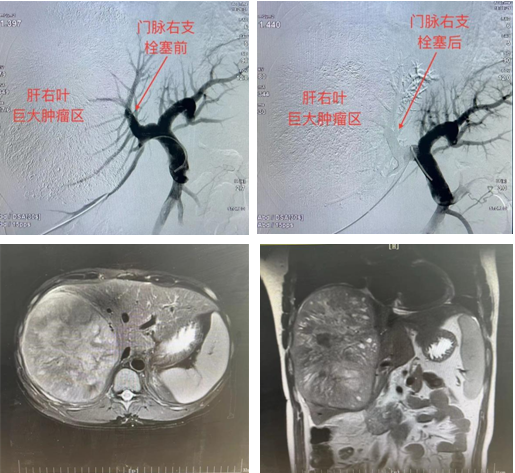

患者32岁男性,确诊肝右叶巨块型肝癌2月余,肿瘤大小已达20×16×13cm,多方打听找到肝胆外科张煜主任。张煜主任组织MDT团队展开讨论,经团队专家会诊后认为,由于肿瘤体积巨大,残余肝脏体积不足,过早进行外科切除很可能导致术后肝衰竭发生。因此在外科术前,首先由微创介入科进行肝动脉化疗栓塞术,控制肿瘤快速进展;第二步,由放疗科进行肿瘤放射治疗,进一步抑制肿瘤生长;第三步,由微创介入科行经皮门静脉栓塞术(PVE)增大残余肝脏体积;第四步,待残余肝脏体积满足外科条件后进行肿瘤切除。

经与患者家属充分沟通、知情告知后,开始实施阶梯式治疗方案。由于前两步治疗的顺利完成,第三步经皮门静脉栓塞术(PVE)也很快实施。PVE术前由超声诊断中心关蕾医师引导,微创介入科颜昭勇医师穿刺门静脉成功,其后微创介入团队先后行门静脉造影、门静脉右支主干及其分支(肿瘤侧)充分栓塞。造影显示肿瘤侧门脉显影消失,提示门脉栓塞成功,手术顺利结束,患者安返病房。

对于肝切除术后剩余肝脏组织不能代偿的肝癌患者,可选择门静脉栓塞术(PVE)。该手术是通过选择性栓塞门静脉、更改门静脉血流,使肝脏非栓塞叶门静脉血流供应及血压增加,栓塞术后栓塞叶萎缩、非栓塞叶代偿性增生的临床技术。该手术的主要栓塞靶血管是即将被切除肝叶的门静脉,使非肿瘤肝叶增生,使原先不能直接手术切除的肝癌患者获得手术切除的机会。门静脉栓塞术的适应证尚无明确定论,目前一般认为:①凡单发或多发的位于肝的一侧,癌体积较大或位置较特殊的原发性肝癌、转移性肝癌、胆囊癌、肝门部胆管癌需做较大的肝切除术者;②由于肝切除后残余肝脏体积(FLR)不足,将出现肝功能衰竭等相关并发症的患者。关于判断指标,现临床采用的方法如下:①对于肝功能正常者,FLR<25%;②对于慢性肝病,FLR<40%,已行全身化疗超过1年者或动脉内化疗超过半年者,FLR<30%。